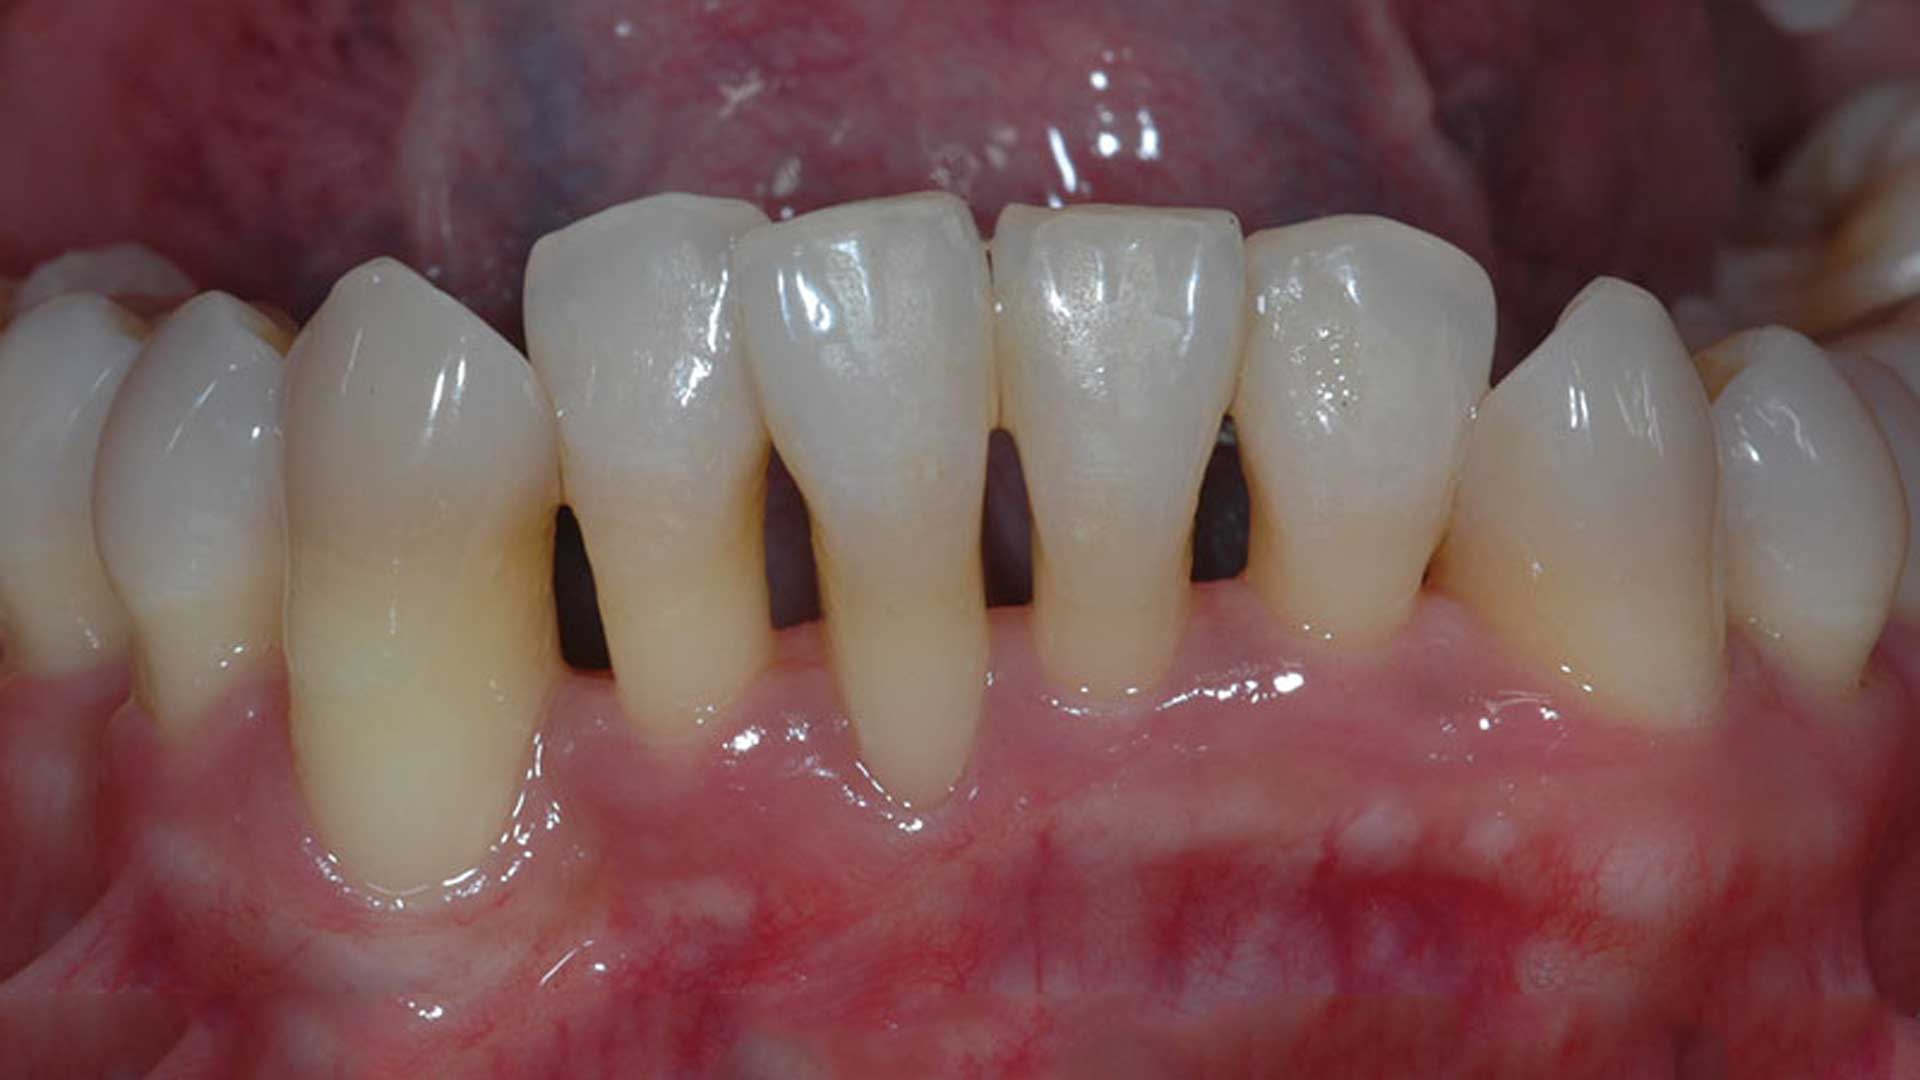

Over time, gum disease causes inflammation in the gums. This inflammation can lead to the gum separating from the teeth, leaving pockets of space open.

Bacteria gather in these pockets, leading to infection and potentially bone loss too. This is the beginning of losing teeth to gum disease, as teeth become weak, unstable and loose.

If you have a receding gum line, then more of your teeth are exposed closer to the roots. This can leave you open to greater risk of inflammation and tooth loss in the future.

Soft tissue grafting is a procedure that lowers the gum line, giving more protection to your teeth by adding tissue from a donor site. This is typically the roof of your mouth.